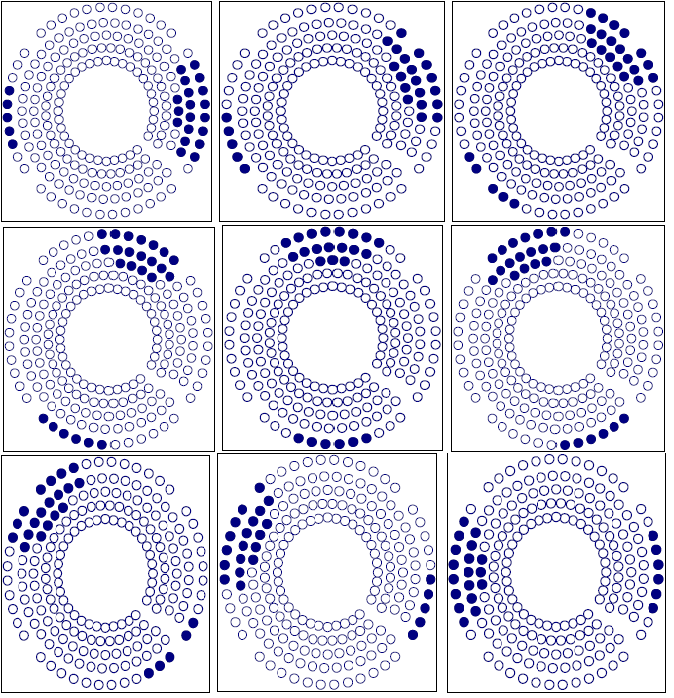

Figure 7 shows the sample point effect on the integral dose calculation by three different trials. The calculation converges at about 100,000 sample points. The number of sample points is determined using an exponential formula. In this setup, we used the integral dose that was calculated by the Monte Carlo method to test the target variation effect on the treatment plan. The Gamma Knife treatment planning system was selected due to the fixed number of beams (201) and fixed geometry of those beams. After checking the convergence of the Monte Carlo calculation, we employed this method to show the sensitivity of the integral dose in beam selection. We fabricated a nine shot Gamma Knife treatment plan with the shot centers midway between inside and outside rings. With a sequence blocking beam treatment for each shot selected, 24 beams were selected to block. There are different possibilities for target variation. A typical case would be the displacement of a target such as an organ at risk. Figure 8 shows three different blocking patterns. Figure 8(a) shows an original setup with 9 plugging shots. Figures 8(b) and 8 (c) show the plugging patterns after the critical structure has been shifted 2 mm superiorly or inferiorly. We developed several mechanisms to compare the different plugging patterns in both the DVH's and treatment patterns. In figure 9, the upper DVH shows the difference due to structure displacement. The circles represent the DVH of the critical region without displacement. The triangles represent the DVH resulting when the critical region is shifted superiorly 2 mm, and the squares represent the situation when the critical region is shifted inferiorly 2 mm. When a blocking beam pattern is used for the treatment, the DVH curves show two features: in one, the dose in the critical structure is significantly lower; in the other, the difference in the three DVH curves decreases and DVH curves nearly overlap each other due to selection of blocking beams. Obviously, displacement of the target leads to variation in the treatment setup. The target DVH curves are not shown because they are overlapped and almost identical for the given resolution in figure 9.

Figure 8a Plugging Pattern of a 9 shot treatment without displacement of the critical structure.

Figure 8b Plugging Pattern of a 9 shot treatment with the critical structure displaced 2 mm superiorly.

Figure 8c Plugging Pattern of 9 shots treatment with the critical structure displaced 2 mm inferiorly.

To show the significance of these differences in the treatment pattern, we devised a formula to describe the distortion. Given the two feature vectors R i MathType@MTEF@5@5@+= feaagKart1ev2aaatCvAUfeBSjuyZL2yd9gzLbvyNv2CaerbuLwBLn hiov2DGi1BTfMBaeXatLxBI9gBaerbd9wDYLwzYbItLDharqqtubsr 4rNCHbGeaGqkY=Mj0xXdbba91rFfpec8Eeeu0xXdbba9frFj0=OqFf ea0dXdd9vqaq=JfrVkFHe9pgea0dXdar=Jb9hs0dXdbPYxe9vr0=vr 0=vqpWqaaeaabiGaciaacaqabeaadaqaaqaaaOqaaiaadkfadaWgaa WcbaGaamyAaaqabaGccaaMc8oaaa@3A94@ , and R j MathType@MTEF@5@5@+= feaagKart1ev2aaatCvAUfeBSjuyZL2yd9gzLbvyNv2CaerbuLwBLn hiov2DGi1BTfMBaeXatLxBI9gBaerbd9wDYLwzYbItLDharqqtubsr 4rNCHbGeaGqkY=Mj0xXdbba91rFfpec8Eeeu0xXdbba9frFj0=OqFf ea0dXdd9vqaq=JfrVkFHe9pgea0dXdar=Jb9hs0dXdbPYxe9vr0=vr 0=vqpWqaaeaabiGaciaacaqabeaadaqaaqaaaOqaaiaadkfadaWgaa WcbaGaamOAaaqabaaaaa@3900@ for the two sets of treatment configurations, which is the plugging beam index, the distortion M( R i , R j ) MathType@MTEF@5@5@+= feaagKart1ev2aaatCvAUfeBSjuyZL2yd9gzLbvyNv2CaerbuLwBLn hiov2DGi1BTfMBaeXatLxBI9gBaerbd9wDYLwzYbItLDharqqtubsr 4rNCHbGeaGqkY=Mj0xXdbba91rFfpec8Eeeu0xXdbba9frFj0=OqFf ea0dXdd9vqaq=JfrVkFHe9pgea0dXdar=Jb9hs0dXdbPYxe9vr0=vr 0=vqpWqaaeaabiGaciaacaqabeaadaqaaqaaaOqaaiaad2eadaqada qaaiaadkfadaWgaaWcbaGaamyAaaqabaGccaGGSaGaamOuamaaBaaa leaacaWGQbaabeaaaOGaayjkaiaawMcaaaaa@3E10@ can be expressed as:

M( R i , R j )=| R i R j R i | MathType@MTEF@5@5@+= feaagKart1ev2aaatCvAUfeBSjuyZL2yd9gzLbvyNv2CaerbuLwBLn hiov2DGi1BTfMBaeXatLxBI9gBaerbd9wDYLwzYbItLDharqqtubsr 4rNCHbGeaGqkY=Mj0xXdbba91rFfpec8Eeeu0xXdbba9frFj0=OqFf ea0dXdd9vqaq=JfrVkFHe9pgea0dXdar=Jb9hs0dXdbPYxe9vr0=vr 0=vqpWqaaeaabiGaciaacaqabeaadaqaaqaaaOqaaiaad2eadaqada qaaiaadkfadaWgaaWcbaGaamyAaaqabaGccaGGSaGaamOuamaaBaaa leaacaWGQbaabeaaaOGaayjkaiaawMcaaiabg2da9maaemaabaWaaS aaaeaacaWGsbWaaSbaaSqaaiaadMgaaeqaaOGaeyOeI0IaamOuamaa BaaaleaacaWGQbaabeaaaOqaaiaadkfadaWgaaWcbaGaamyAaaqaba aaaaGccaGLhWUaayjcSdaaaa@4927@

This calculation shows that the distortion is 28% when the critical region is shifted superiorly 2 mm, and distortion is 24% when the critical region displaced inferiorly 2 mm. The difference in these percentages is a result of differences in the helmet's distance from the target.